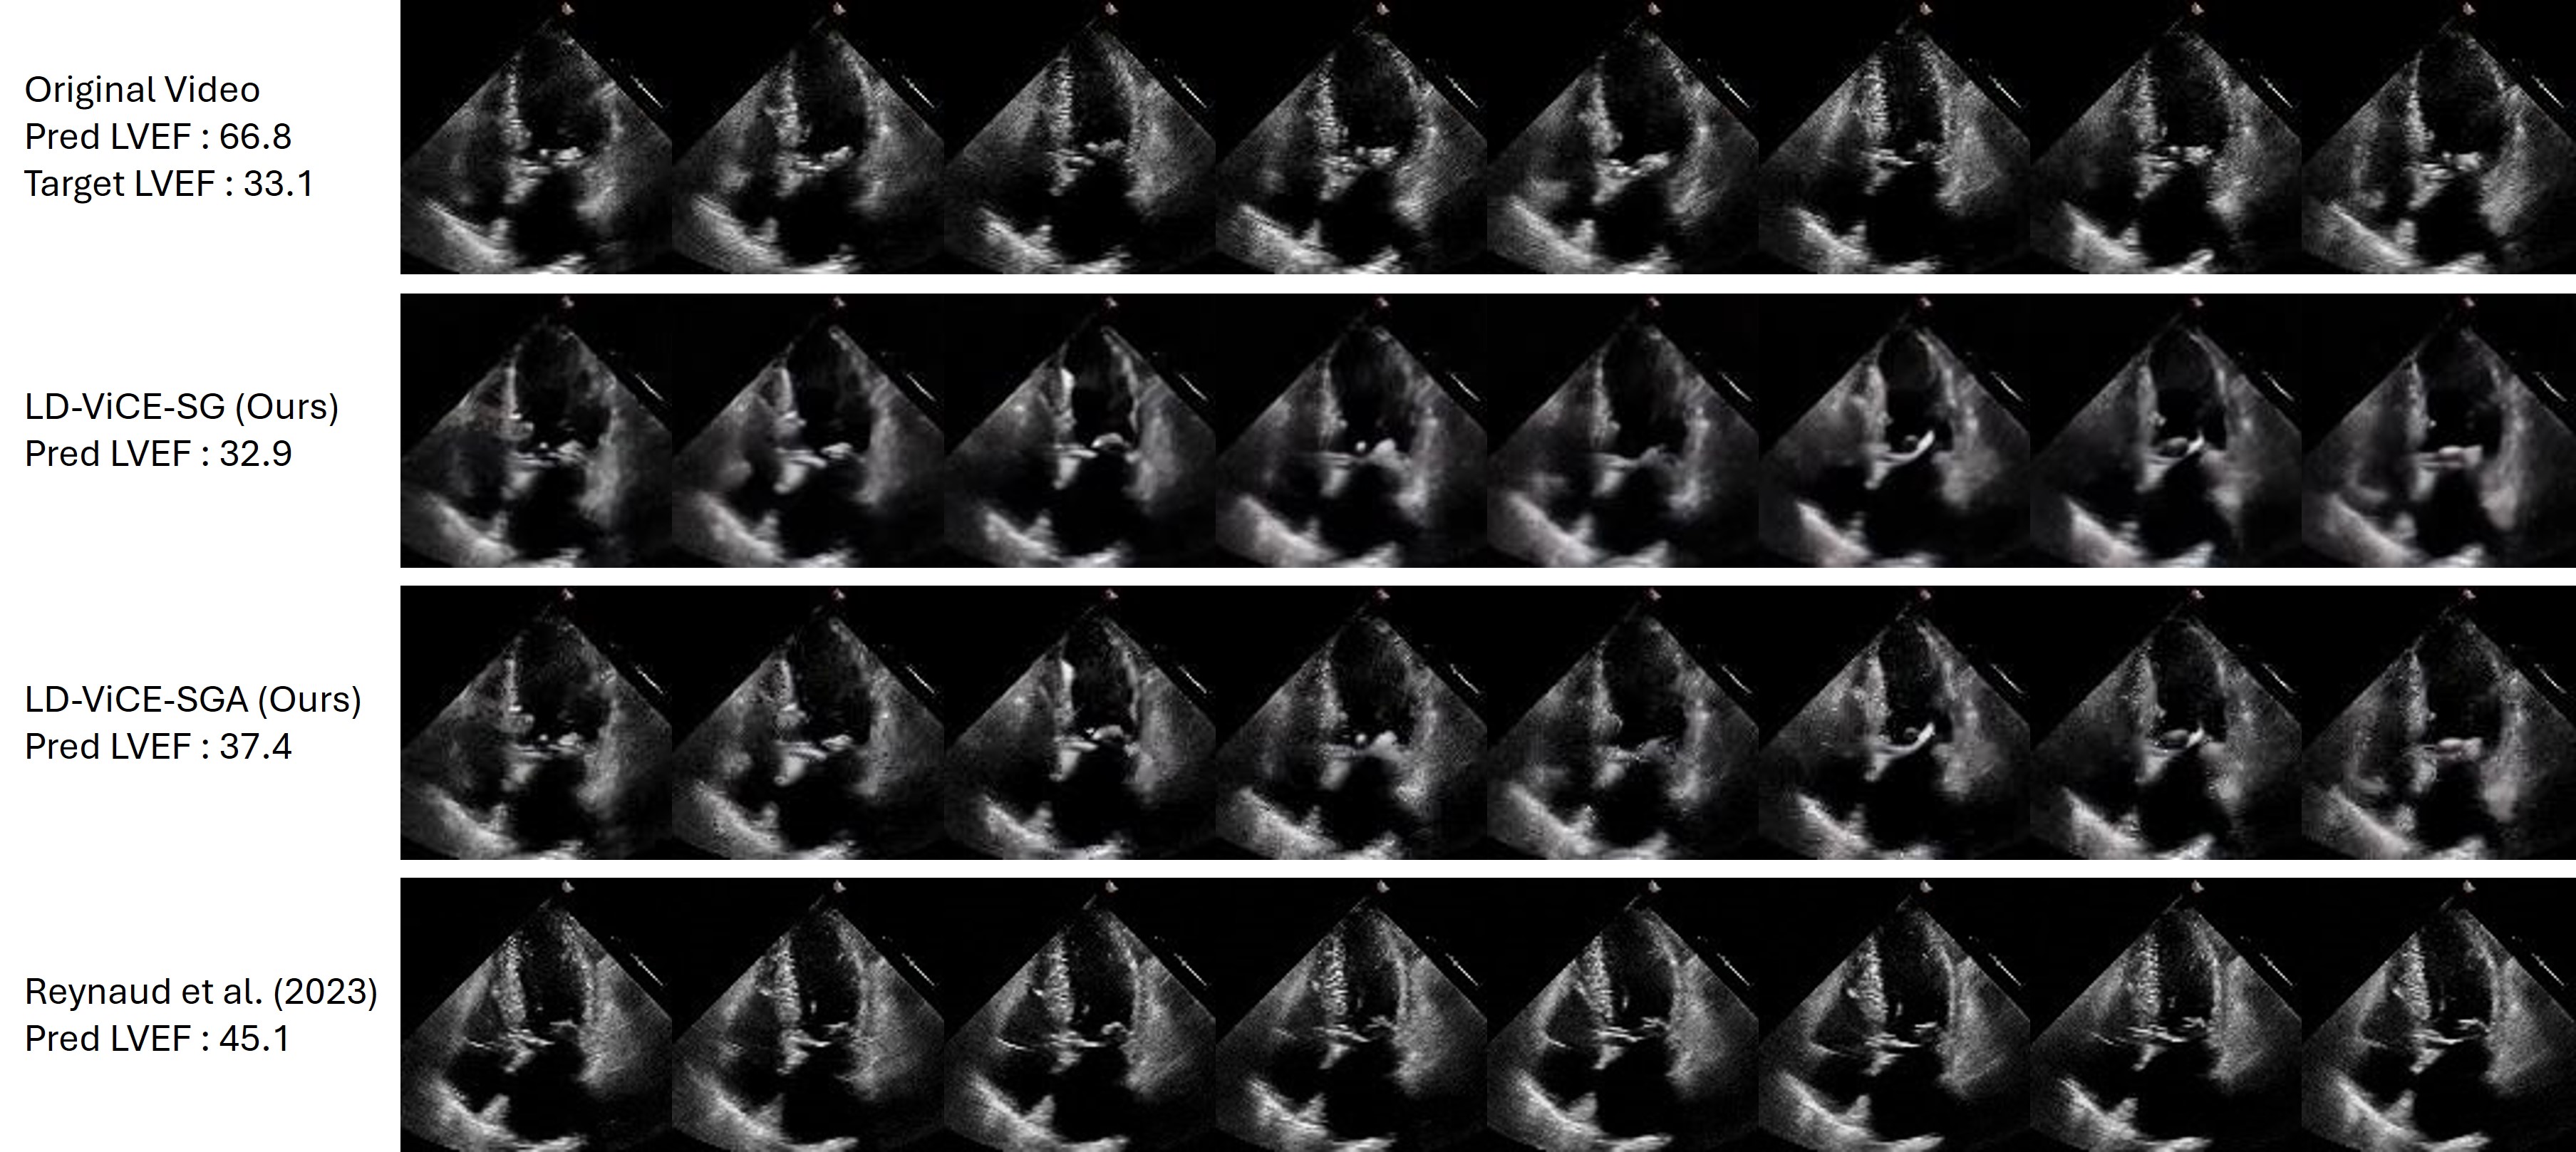

Figure 7 and 8 provide a qualitative comparison on the EchoNet-Dynamic dataset, highlighting LD-ViCE’s ability to generate counterfactual explanations that are better aligned with the target regression values compared to baseline methods. The results illustrate both the effectiveness of classifier-guided generation and the visual fidelity of the produced counterfactuals.

Refer to caption

Figure 7: Qualitative comparison of counterfactual explanations on the EchoNet-Dynamics dataset, demonstrating LD-ViCE’s improved alignment between counterfactual explanations and target regression values. The first row displays eight frames from the original video, while the following rows show counterfactuals generated using LD-ViCE-SG, LD-ViCE-SGA, and EchoDiffusion (Reynaud et al. 2023), respectively. The predicted and target LVEF values are given on the left.

Figure 8: Qualitative comparison of counterfactual explanations on the EchoNet-Dynamics dataset, demonstrating LD-ViCE’s improved alignment between counterfactual explanations and target regression values. The first row displays eight frames from the original video, while the following rows show counterfactuals generated using LD-ViCE-SG, LD-ViCE-SGA, and EchoDiffusion (Reynaud et al. 2023), respectively. The predicted and target LVEF values are given on the left.